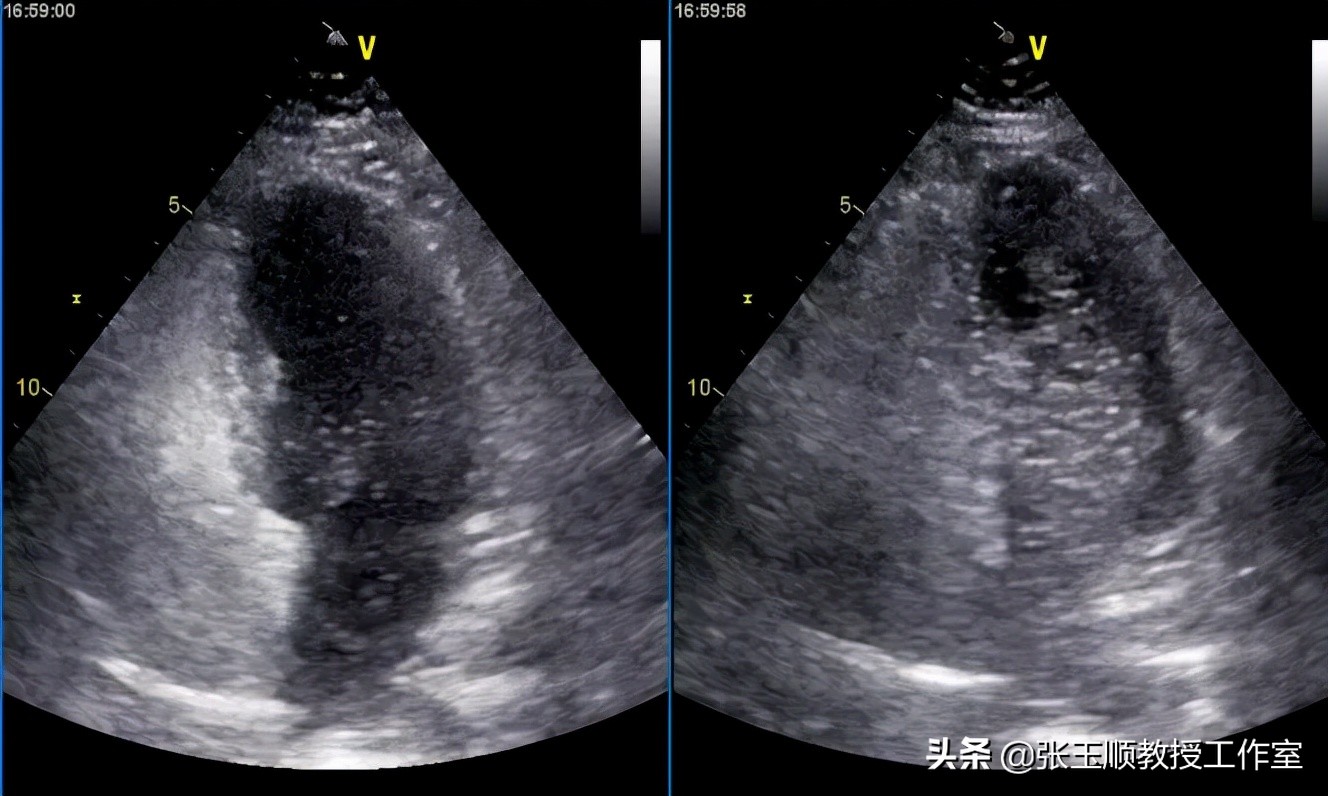

医院立即给李先生安排了发泡试验检查,果然发现静息状态下左心就有中到大量微气泡显影(40-50个/帧),行Valsalva动作后,即刻左心内有大量微气泡,整个心腔都浑浊。这样李先生很可能就有卵圆孔未闭了(图1)。

图1 发泡试验左心大量微气泡